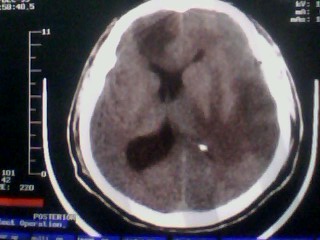

以下是引用随光逐影在2010-1-7 14:49:00的发言:[br]1)结合病史,考虑多发性脑转移瘤可能性大;建议行ct增强扫描检查。2)大脑镰下疝。3)脑积水。